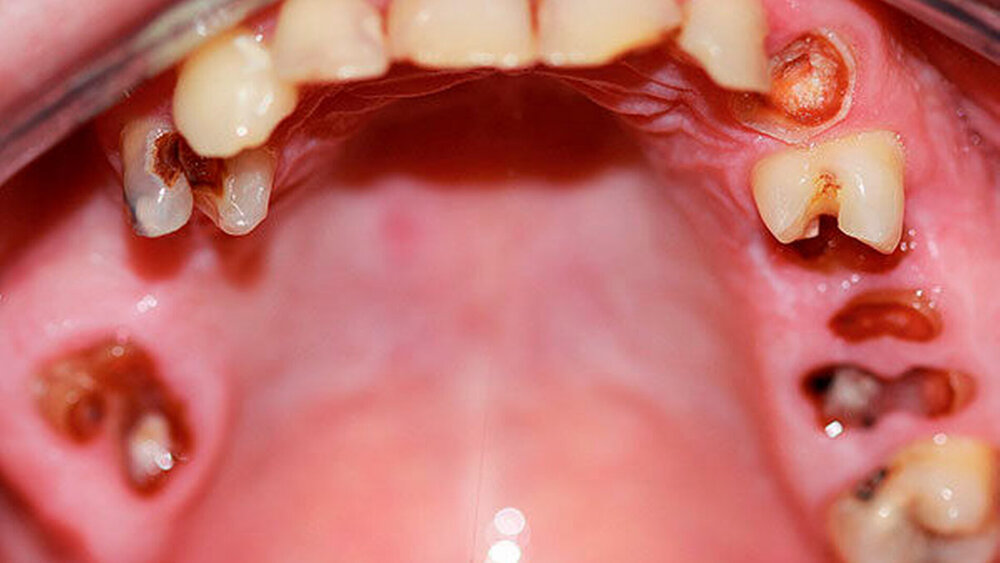

Bei chronischem Crystal-Meth(CM)-Konsum wurde eine Vielzahl körperlicher und psychischer Langzeitwirkungen, beispielsweise Herz-Kreislauf-Erkrankungen, strukturelle Hirnschädigungen und Persönlichkeitsveränderungen, beobachtet [Hamamoto et al., 2009]. In der aktuellen Literatur werden außerdem schwerwiegende Auswirkungen auf die Zahn-, Mund- und Kieferregion beschrieben [Hamamoto et al., 2009; Rhodus et al., 2008]. In den USA, wo nach Schätzungen knapp ein Drittel der weltweit über 30 Millionen CM-Abhängigen lebt, wurde 2005 erstmals der Begriff des „Meth mouth“ in der Fachliteratur genannt [Hamamoto et al., 2009; Rhodus et al., 2005] (Abbildung 1). Dabei wurden fünf Kardinalsymptome beschrieben: 1. Grassierende Karies (Abbildungen 2 und 3), 2. Gingivitis und Parodontitis, 3. Xerostomie, 4. Bruximus und 5. Trismus [Hamamoto et al., 2009; Rhodus et al., 2008].